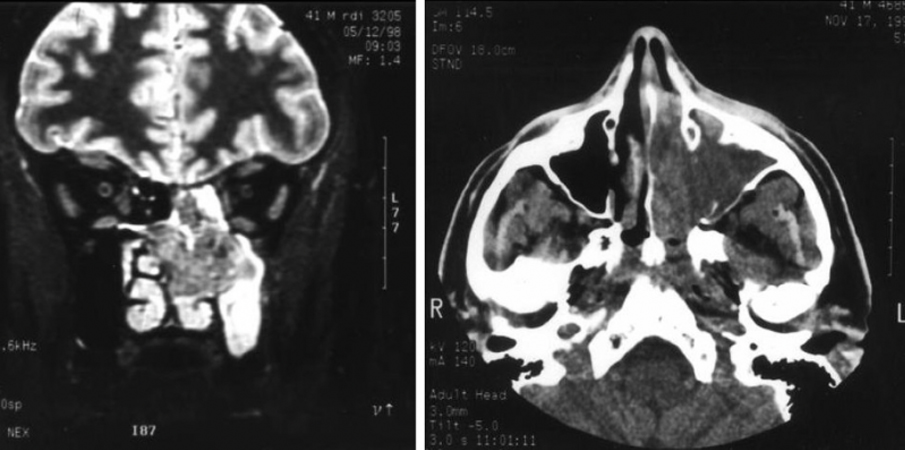

Fig. Deviazione ossea destra del setto nasale.

TAC: deviazione destro convessa del setto nasale (indicata dalla freccia).

Nella TAC la persona guarda verso di noi.

TAC: altre deviazioni destro convesse del setto nasale

Tumore maligno. Adenocarcinoma etmoidale sinistro.